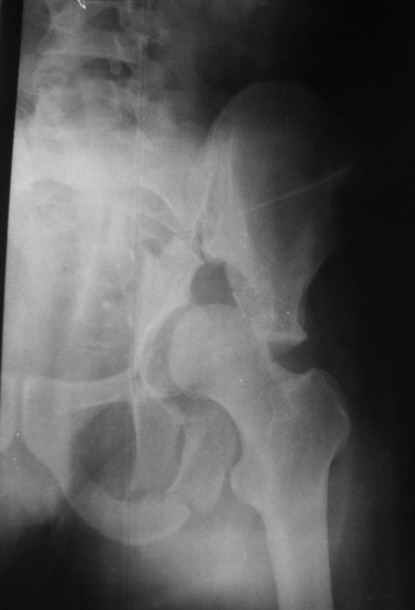

Here's a 25ys old man, who sustained this fracture 2 ys ago. He was operated on with a double approach, ilioinguinal and KL approach, but I don't know why was fixed only with a posterior recon plate.

Obviously the reduction was not good and the fixation failed with also an infection. After 1 year the plate was removed and the infection healed. Actually there are no signs of infection but we should do something. My option is the following:

Reduction and ORIF of the acetabular gap (I think fixation of both columns) and THR with the headas bone graft.

My question is: which are the tricks to reduce that fracture at 2ys?

Osteotomies of pubic and ischiatic ramus are sufficient?

Should I start with the KL or with the ilioinguinal approach (while making the osteotomies?

What about the wide Letournel approach?